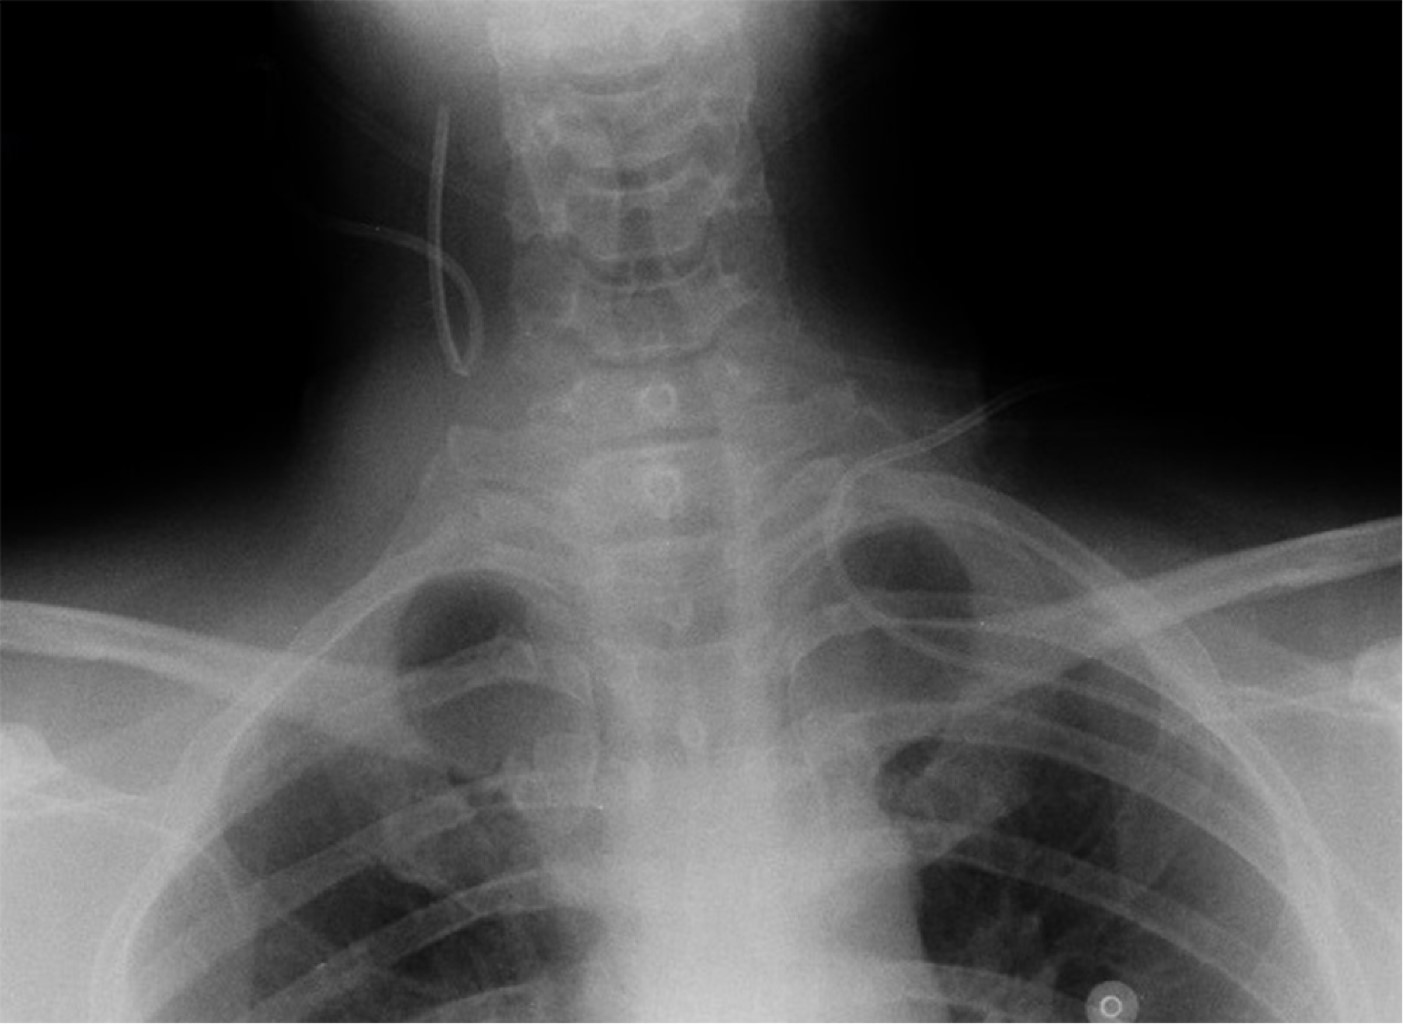

Malposition of central venous catheters is associated with important and underestimated risks. Although some factors have been related with malposition, its cause is generally not diagnosed, and it seems to have multifactorial origin. We present two cases of central venous catheter malposition due to unusual anatomical causes, diagnosed in the perioperative period. In the first case, superior vena cava agenesis was diagnosed during mitral replacement by sternotomy, which was logically associated with malposition of the inserted central line. The use of catheters and devices through jugular and subclavian veins in patients with this infrequent pathology is associated with important limitations and serious potential complications. In the second case, an undiagnosed goiter causes bilateral and simultaneous malpositioning of two inserted central venous catheters, in the context of an emergency situation, in both internal jugular veins.

Figure 1